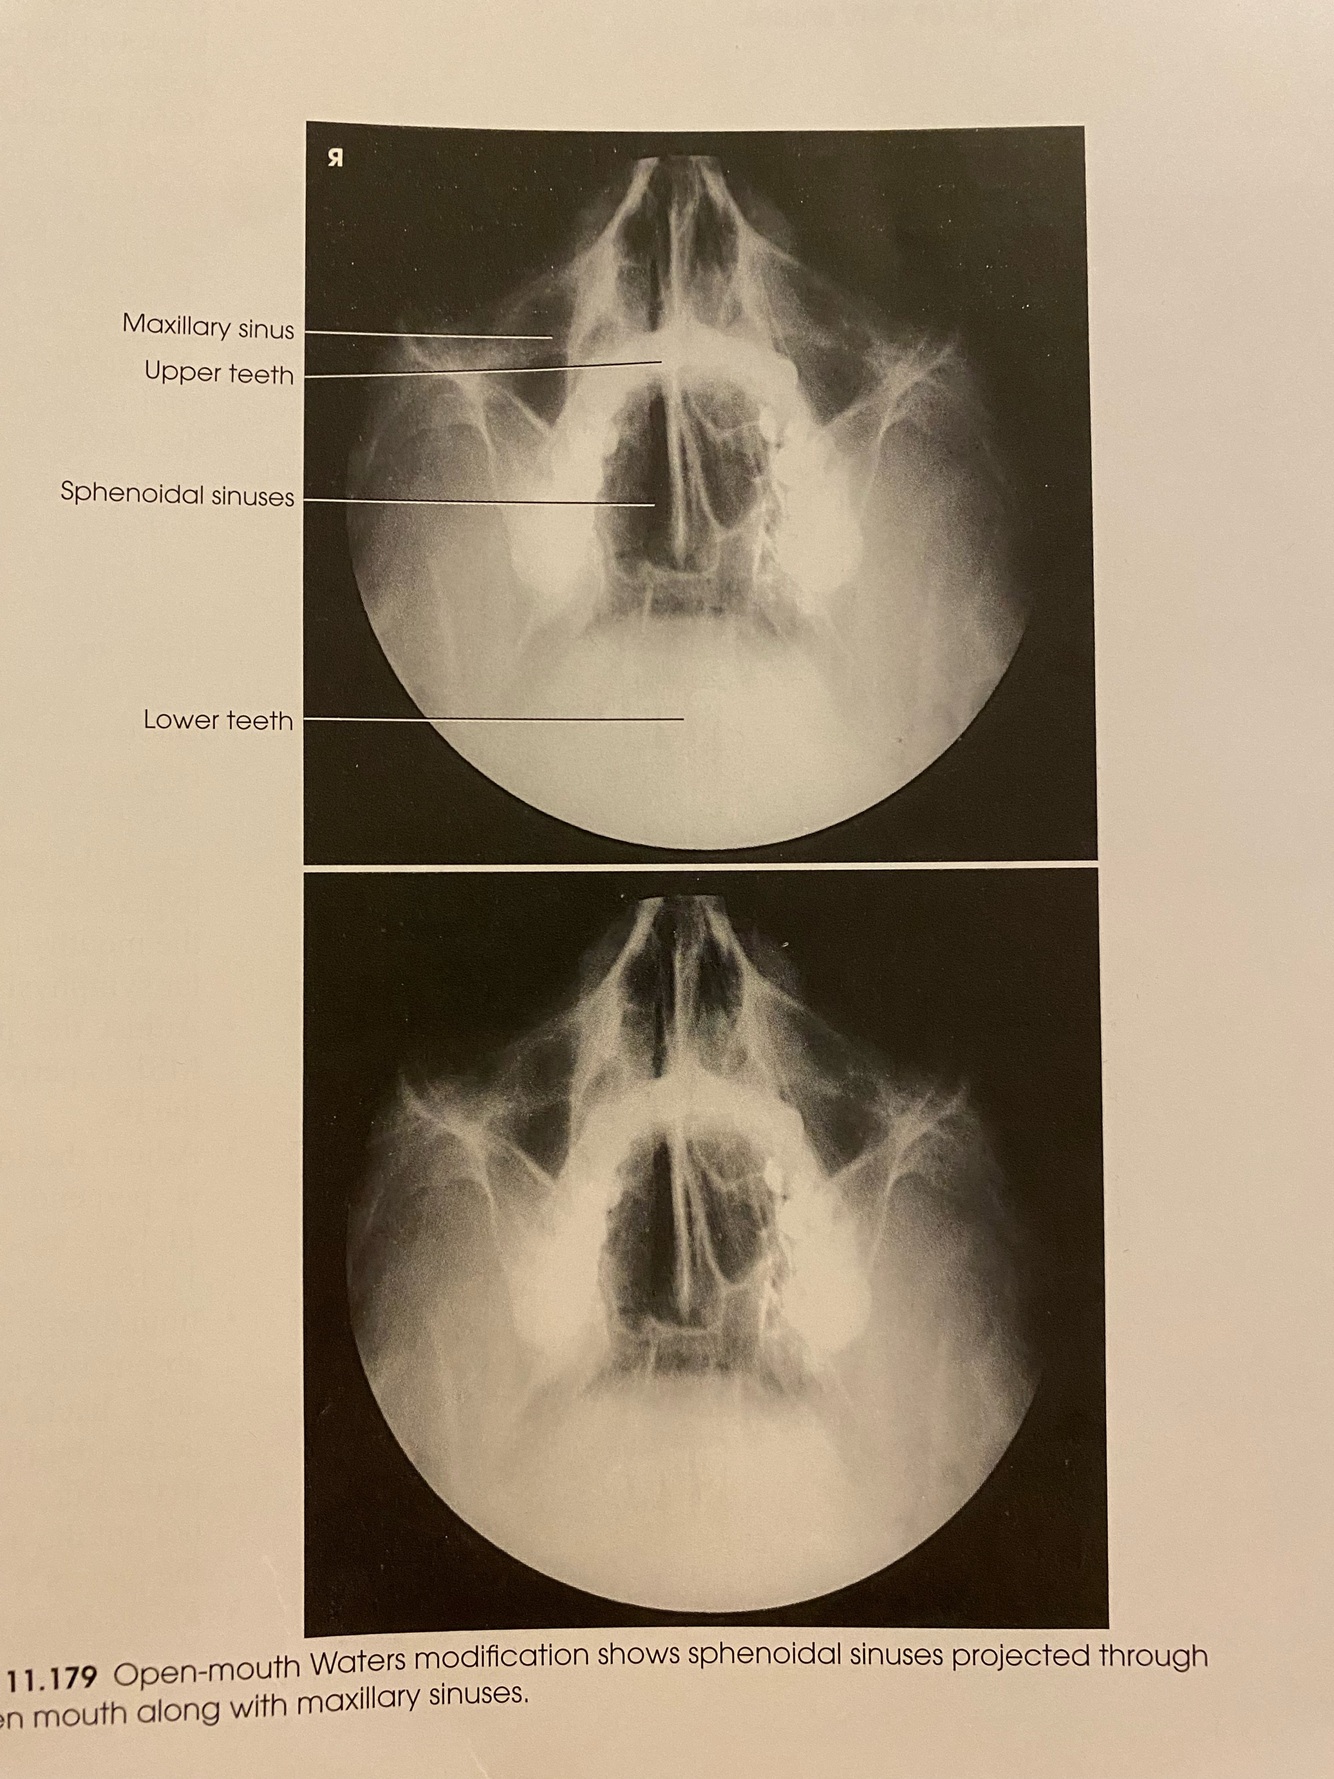

PARIETALCANTHIAL WATERS (OPEN MOUTH) Positioning

A

-MSP is ⟂ to IR

-OML forms an angle of 37º from plane of IR

-MML is approximately ⟂ to IR

-CR: perpendicular exiting the acanthion

-Place patients chin on the grid adjusting the neck so that the MML is perpendicular to the IR, open mouth

-Respiration: suspend

18

Q

PARIETALCANTHIAL WATERS (OPEN MOUTH) Evaluation Criteria

-Proper collimation

-Sphenoid sinuses projected through the open mouth

-Maxillary sinuses

-OML in proper position

-Petrous pyramids lying inferior to the floor to the maxillary sinuses

-No rotation or tilt

-Equal distances from lateral borders of skull to lateral borders of orbit on both sides

-Orbits and maxillary sinuses symmetric

-MSP of head aligned with long axis of field

19

26

Which projection shows the Maxillary AND Sphenoidal sinuses?

Parietoacanthial (Waters) OPEN MOUTH